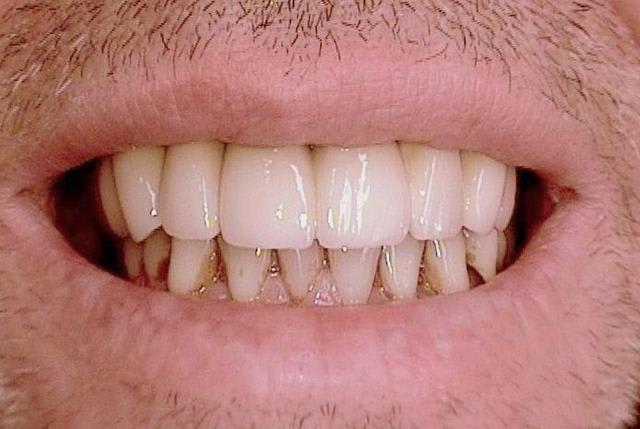

J ai planté à 60 Ncm sans fracturer le septum.Juste après l opération , les prep caps en zircon ont été cémenté.La restauration définitive 34 jusqu` à 37 été fixé 2 semaines après l implantation avec implantlink (detax). Après un an, le bridge a été retiré facilement pour voir l´état de la gencive et faire une radio de contrôle.On la re ossifiction est satisfaisante et que la gencive "aime" le zircon.

Le bridge a ensuite été recémenté sans correction nécessaire du bridge.

merci pour ton commentaire.Malheureusement je ne comprends pas bien de quoi tu veux parler (Occlusion?) . Le concept d occlusion c est d avoir un guide de "groupe" , chaque dent a une occlusion de 8 micrometers (Shim stock) avec ses antagonistes.

ah je comprends mieux!!! :-),les "espaces" que tu vois ce sont des prep caps en zircon avec prothèse zircone il n y donc pas d accumuation de plaques sinon tu aurai raison ! (bonne remarque). La couronne ne touche pas" l assiette" (en allemand on parle d assiette...)du prep cap ...

-il n y a pas d accumulation de plaque quand on n utilise du zircon

-les "espaces" sont sugingivales

-les prep caps sont des couronnes en zircon pré fabriquées et ce n est pas nécessaire d avoir les extrémites des couronnes jusqu à la base des prep caps , meme si les couronnes sont dans une position termine-tangentiale

-la base des prep caps dans ce cas là sont environ 4/5mm subgingival, donc après avoir cémenté les bridges on ne pourrait pas nettoyer le cement si la couronne allait jusqu´à la base des prep caps.

-Enfin ici il s ´agit de plusieurs implantations immédiates durant lesquelles j utilise toujours les prep caps.